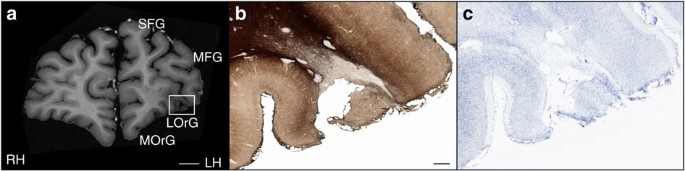

Кое-что разглядеть удалось (вы видите показанные поражения стрелкой), однако полную картину ученые так и не получили. Только после смерти мозг Молисона вновь был подвергнут испытаниям: сначала он, в зафиксированном состоянии был изучен на трёх- и семитесловом томографе, что дало исключительное качество картинки (см. фото внизу), а затем исследователь Джакомо Анезе совершил настоящий научный подвиг: 53 часа резал на микротоме замороженный мозг Молисона на 2401 срез толщиной в 70 микрон каждый. Удивительно, что исследователь «запорол» только два образца. И теперь ученые смогли построить полную карту поражений мозга Молисона.